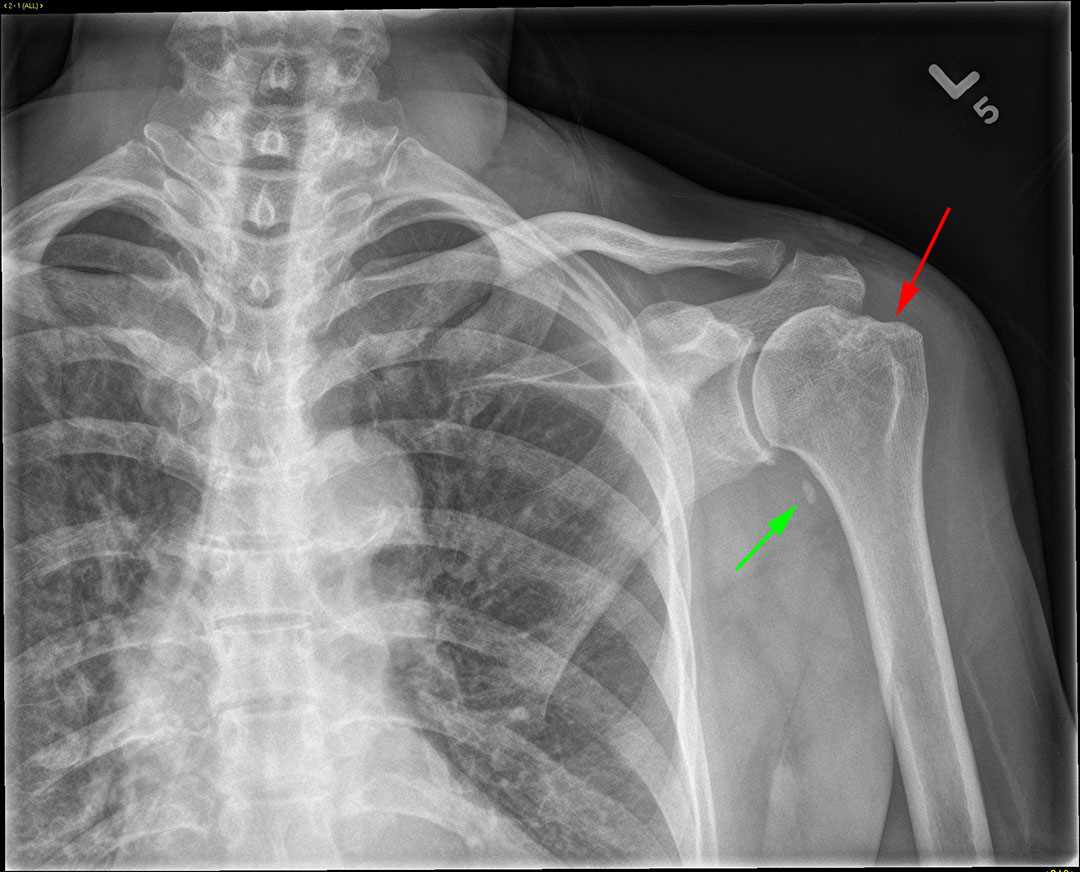

Bankart HillSachs lesions What Is A Hill Sachs Lesion Learn about the risk factors,. Learn about its epidemiology, etiology, classification, clinical. Learn about the signs, causes and options for surgery. A hill sachs lesion is a bone defect on the humeral head caused by anterior shoulder dislocation. Learn how to diagnose, classify, and. It is often associated with a bankart lesion of the glenoid,. Learn how to diagnose and. What Is A Hill Sachs Lesion.

HillSachs and Bankart Lesions wikiRadiography What Is A Hill Sachs Lesion It is often associated with a bankart lesion of the glenoid,. Learn about its epidemiology, etiology, classification, clinical. A hill sachs lesion is a bone defect on the humeral head caused by anterior shoulder dislocation. Learn how to diagnose and treat this condition with. Learn how to diagnose, classify, and. Learn about the risk factors,. Learn about the signs, causes. What Is A Hill Sachs Lesion.

HillSachs and Bankart Lesions wikiRadiography What Is A Hill Sachs Lesion A hill sachs lesion is a bone defect on the humeral head caused by anterior shoulder dislocation. Learn about the signs, causes and options for surgery. Learn about the risk factors,. It is often associated with a bankart lesion of the glenoid,. Learn how to diagnose and treat this condition with. Learn about its epidemiology, etiology, classification, clinical. Learn how. What Is A Hill Sachs Lesion.